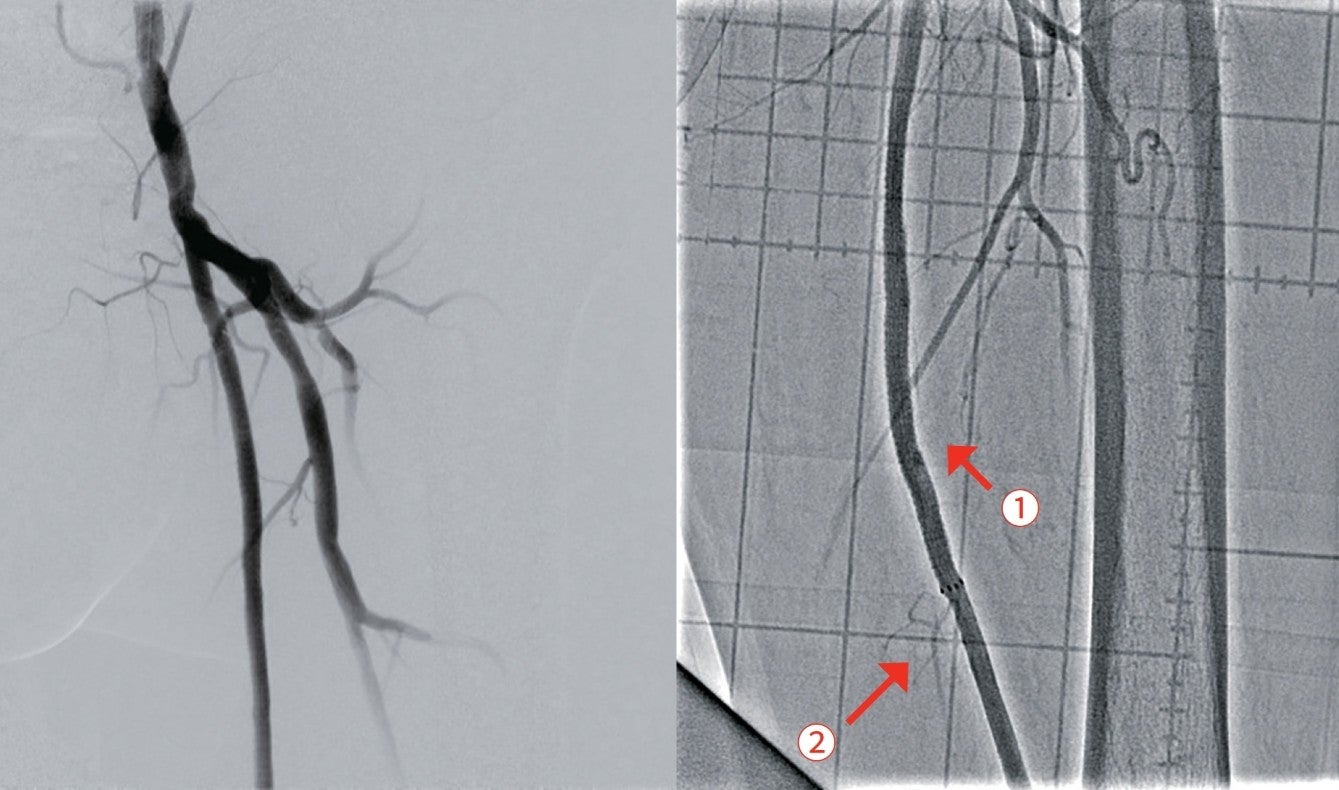

前拡張後の造影で温存したいコラテ部分に解離が認められ(図2)、また、IVUSでヘルシーランディングが可能な位置を確認したところ、遠位部のコラテ(図1矢印②)を温存してヘルシーランディングができることを確認できた。さらにIVUSで血管径を確認し、同等サイズのバイアバーン® ステントグラフトを留置した。バイアバーン® ステントグラフトが展開し始めた後、展開ラインをゆっくり連続した動作で引くようにするとバイアバーン® ステントグラフトの位置がずれることなく留置することが可能であった。その後、バイアバーン® ステントグラフト全長を同径のバルーンで高圧後拡張してIVUSでバイアバーン® ステントグラフトが充分拡張されていることを確認し、手技を終了した。(図3)

実際、前拡張に径6.0 mmのロングバルーンを用いて長時間拡張を行ったところ造影上、長い解離が明らかで、IVUS上もプラークの圧縮は不充分であった。ベアメタルステントでの長期予後が期待できないこと、薬剤コーティングバルーン(DCB)を使用するには解離が大きいことや保険償還の観点から、当症例でのデバイス選択としてはバイアバーン® ステントグラフトが長期予後を期待できると考えた。

当症例は比較的石灰化の少ない長区間のCTO症例であり、臨床成績の観点や長さ20 cm以上の病変に対しても薬事適応が認められているデバイスであるという観点もふまえて、バイアバーン® ステントグラフトを選択した。当症例において、IVUS所見からは血管径が6.0 mmあり小血管ではないことや、留置位置となるレファレンス上下ともヘルシーランディングが可能かを確認したうえで、バイアバーン® ステントグラフトを留置した。コラテラル血管の温存が悩ましい症例であったが、より遠位部のコラテラル血管も温存できることもあり、ヘルシーランディングを重視し、コラテ血管をバイアバーン® ステントグラフトでカバーし、病変をフルカバーすることで再狭窄の懸念も少なく、長期予後を期待できると考えた。

また、デバイス留置に際しても、上下の位置をピンポイントで決めて留置しやすく、留置位置がずれる心配が少ないこともバイアバーン® ステントグラフトの魅力の一つであると考える。